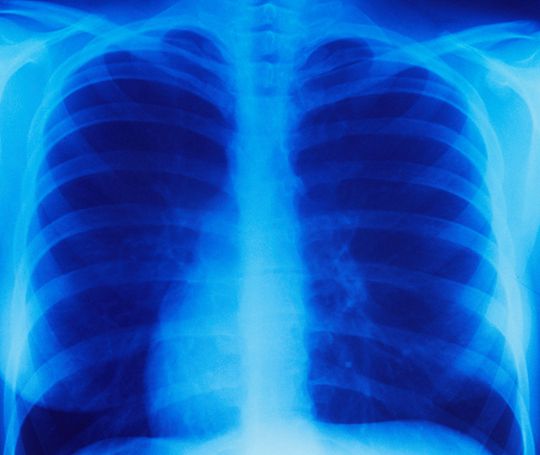

2. 影像检测:X光可能会显示异常肿块或结节,但CT扫描可以显示出肺部可能无法在X光上检测到的小病灶。